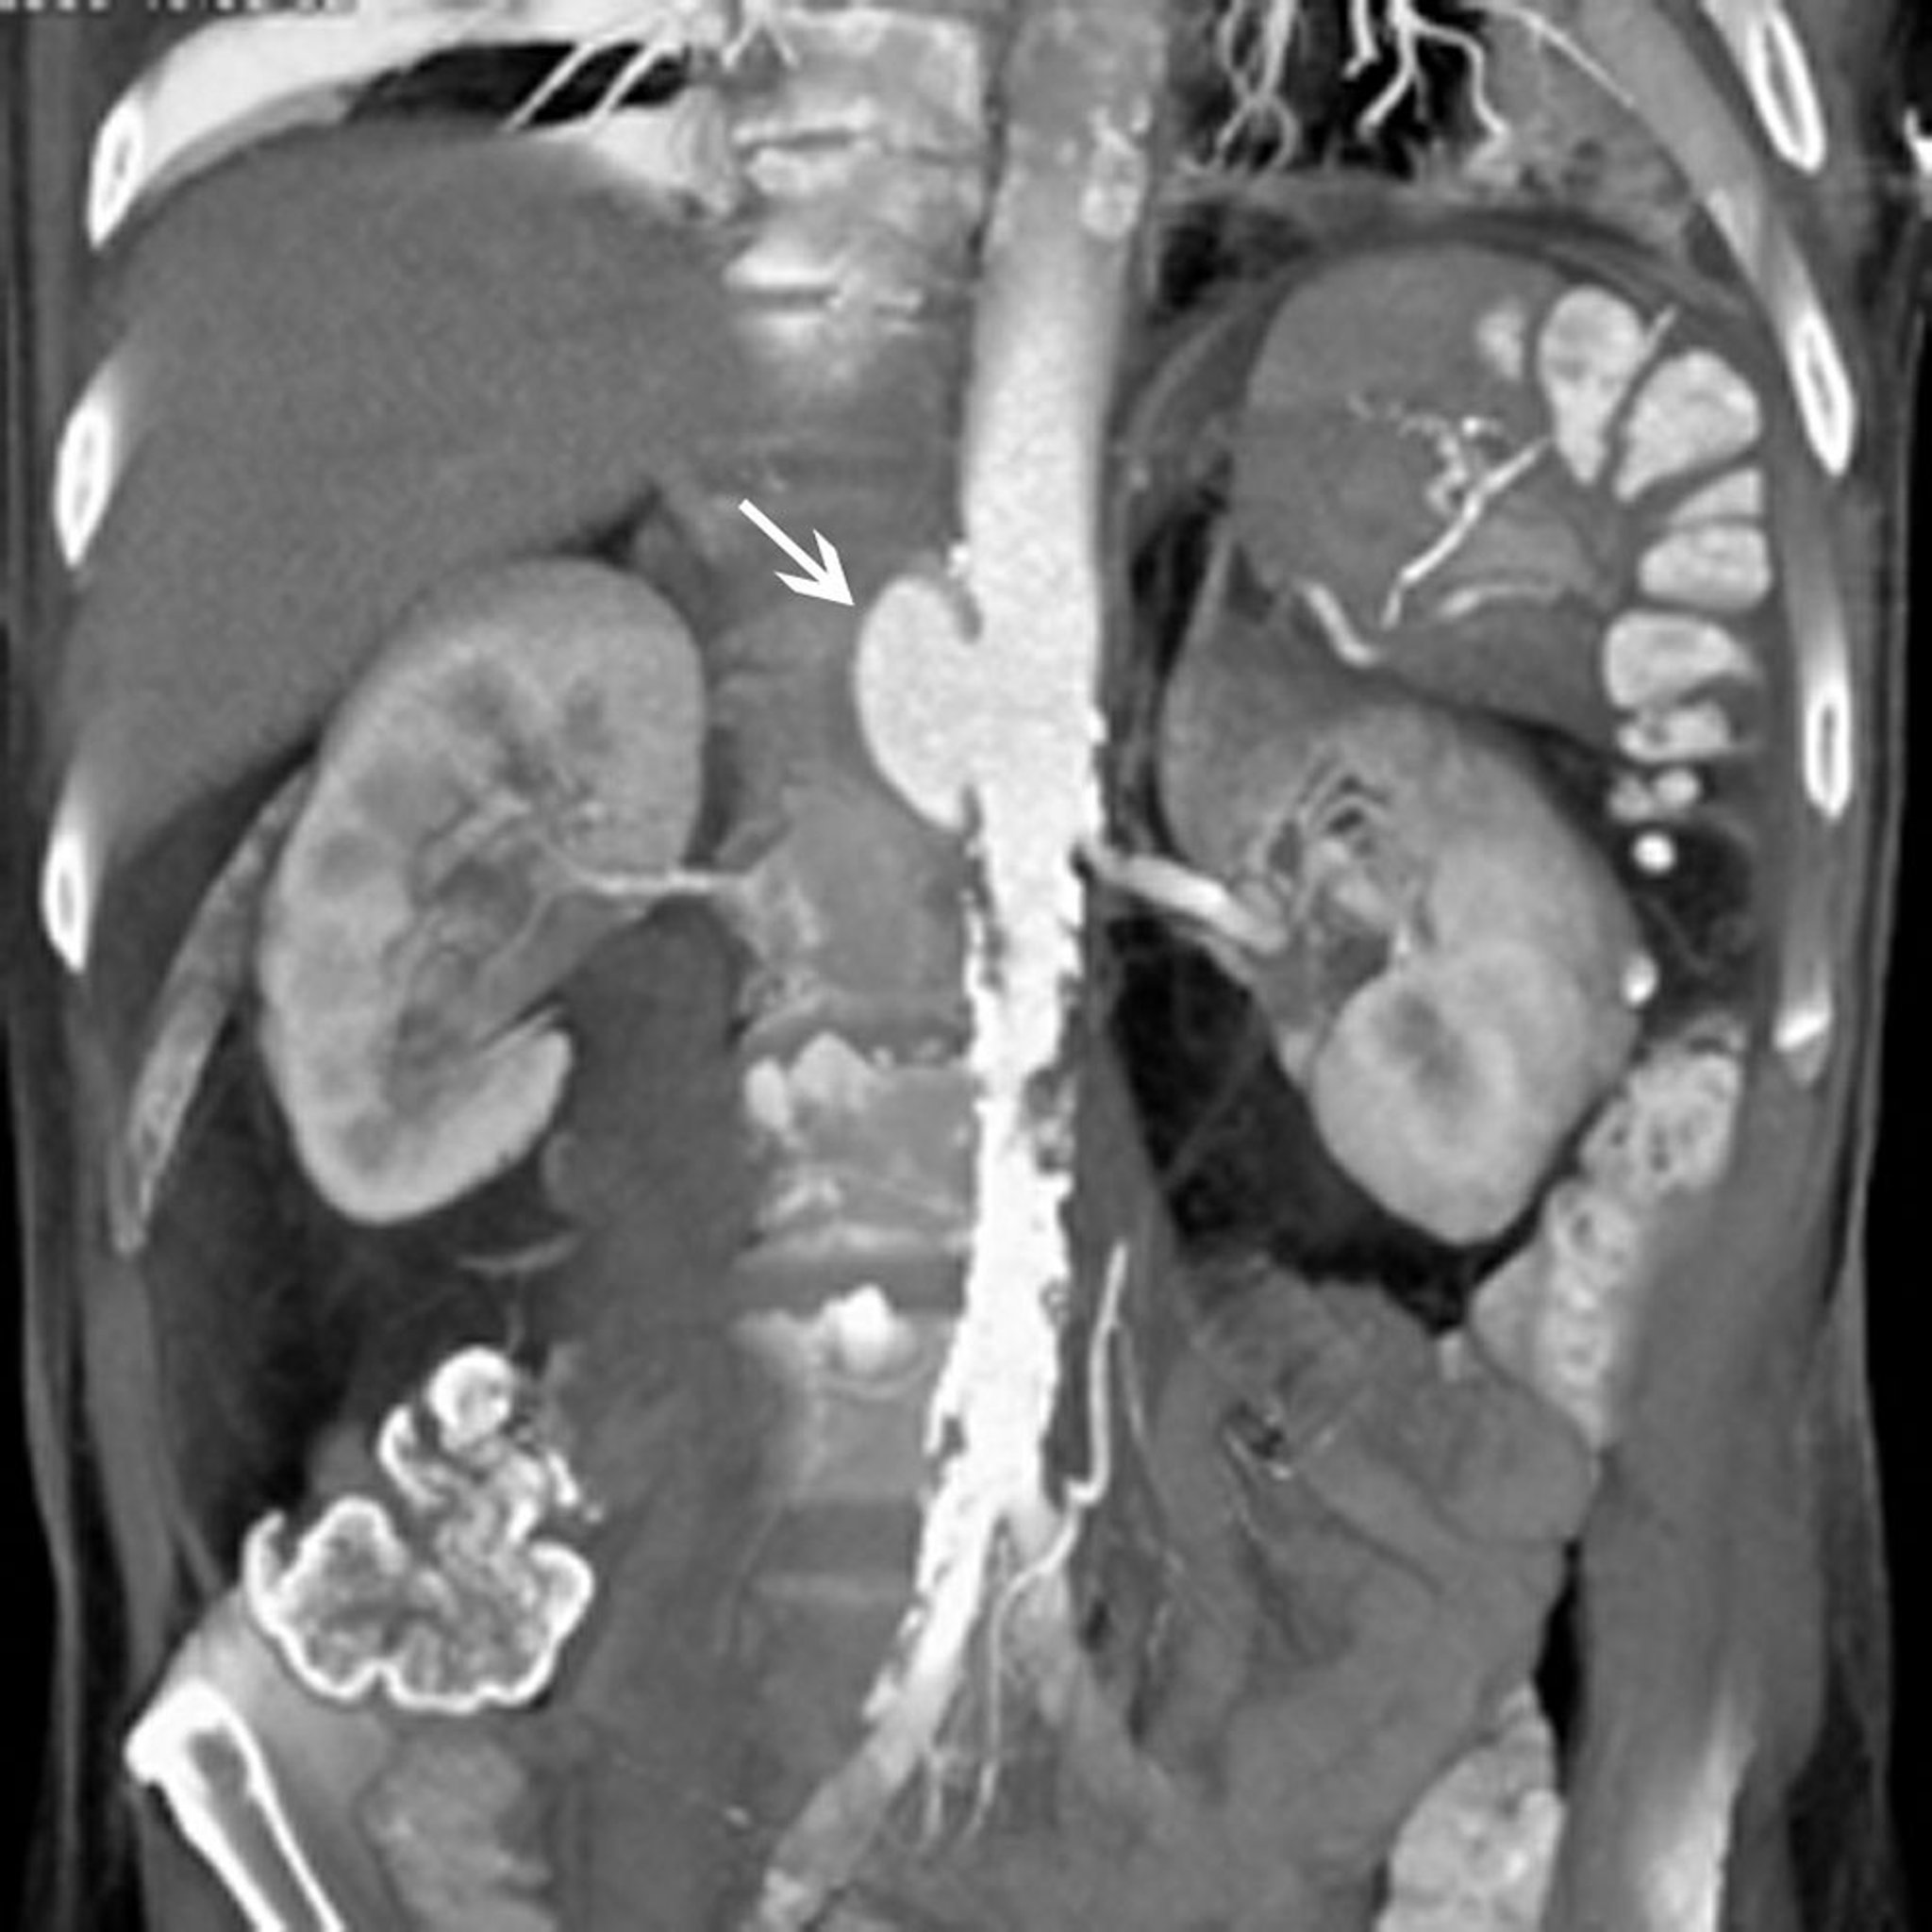

Seudoaneurisma aórtico abdominal (TC)

La flecha blanca muestra un seudoaneurisma aórtico abdominal suprarrenal. También hay una extensa placa en la aorta infrarrenal y las arterias ilíacas.